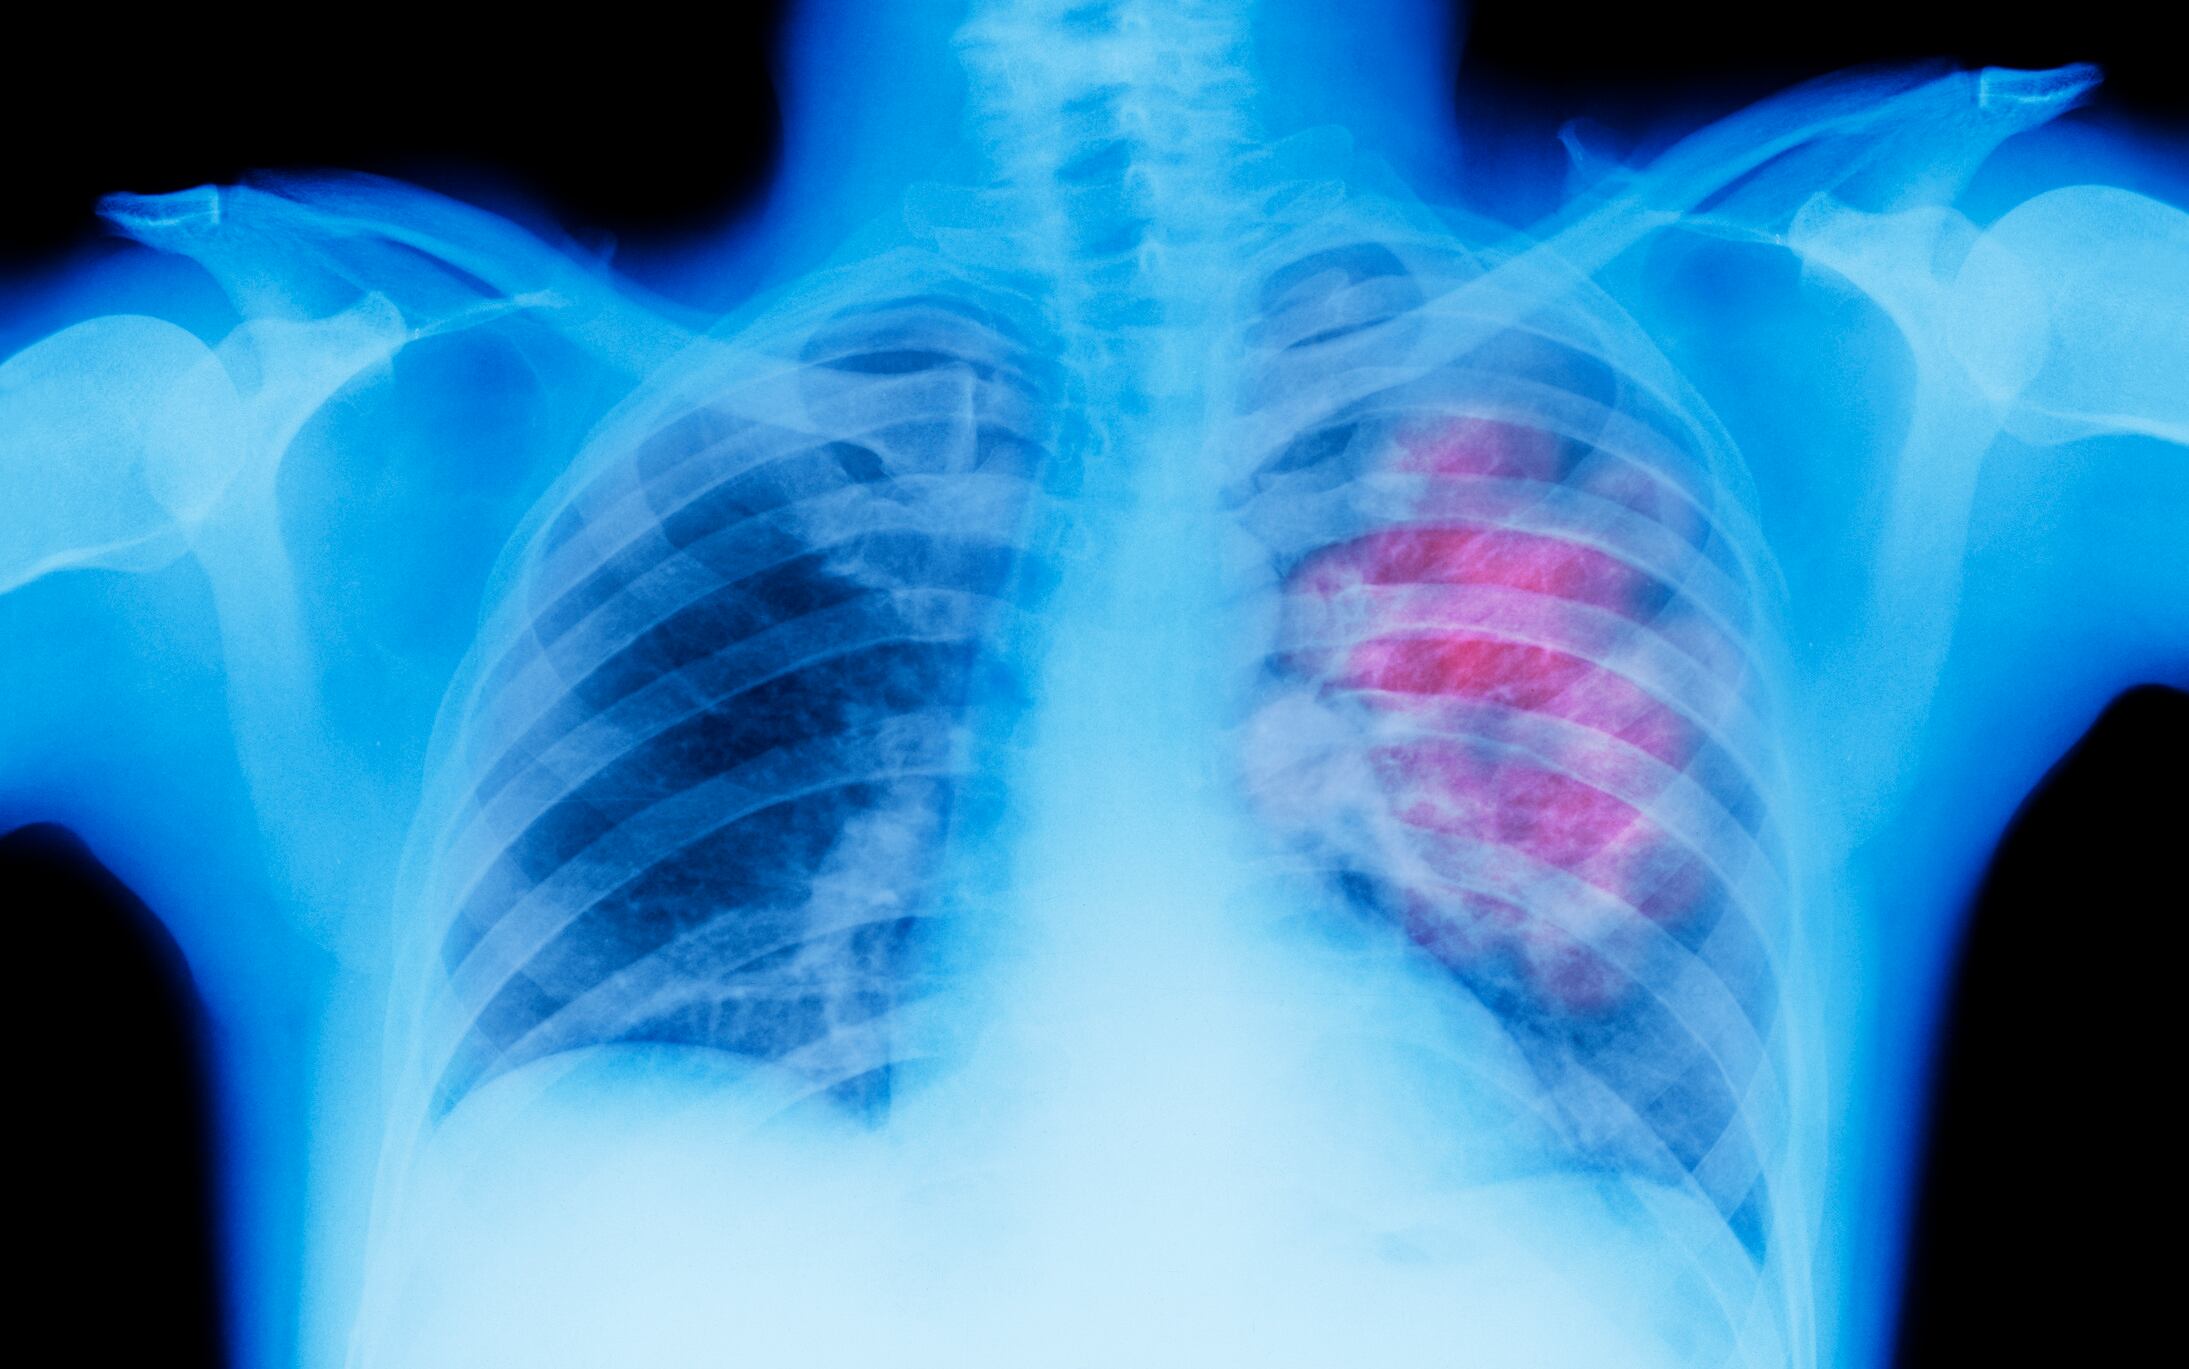

Imagen de referencia. Foto: Getty Images / Peter Dazeley

La especialista explicó que el cáncer de pulmón se consolida como la principal causa de muerte oncológica a nivel mundial, el cual en Colombia ha mostrado un incremento alarmante. Aunque históricamente ha sido la principal causa de muerte en hombres, también ocupa el segundo lugar en mujeres.

Si bien el factor de riesgo más significativo es el consumo de tabaco, que se asocia directamente con el 85% de los casos de cáncer de pulmón, existen otras variables que merecen igual atención, muchas de las cuales son controlables y contribuyen a la preocupación sobre la salud pulmonar.